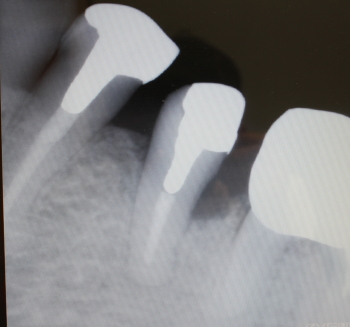

骨補填剤充填後のX-ray

2016年07月21日撮影

術後約3.5カ月後

予後良好